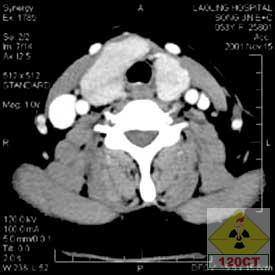

雙期增強掃描雙期增強掃描雙期增強掃描是指利用螺旋CT掃描速度快的優點,在一次靜脈注射對比劑後根據檢查器官的血供特點,分別於強化的不同時期對檢查的器官進行兩次或多次完整的螺旋掃描。

雙期增強掃描 - 方法 先平掃,設定增強掃描的範圍以及兩次或多掃描開始時間,掃描參數與平掃相同,經靜脈用電動壓力注射器注入對比劑80ml~100ml,3ml~4ml/s,對比劑注射完後與掃描開始時間同步。

25s~30s肝臟動脈期肝硬化患者開始掃描時間要晚一些

60s~70s肝臟門靜脈期

120s肝實質平衡期 胰腺 25s~30s胰腺動脈期